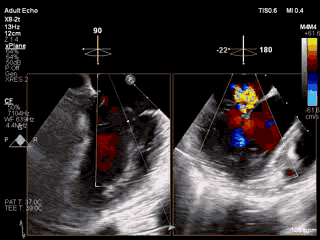

视频1 经皮二尖瓣夹合术中经食道超声心动图证实术前诊断,即二尖瓣后叶腱索断裂、脱垂(P2为主,累计部分P1)伴重度关闭不全

视频4 在食道超声心动图引导下于二尖瓣P2区植入一枚MitraClip XTR夹合器后二尖瓣关闭不全减轻,但夹合器内侧仍存在反流

4月11日上午患者在全麻下接受MitraClip经皮二尖瓣夹合术。术中穿刺右股静脉,经食道超声心动图(TEE)再次评估瓣膜病变(视频1),并引导顺利穿刺房间隔(视频2)。随后送入二尖瓣夹合系统,在TEE引导下于二尖瓣P2区植入MitraClip XTR夹合器一枚(视频3),二尖瓣关闭不全减轻,但夹合器内侧仍存在反流(视频4)。团队决定为患者植入第二枚夹合器(MitraClip NTR),手术过程顺利(视频5)。TEE三维显示在植入第二枚NTR夹合器后,二尖瓣呈双孔启闭,两枚夹合器位置、结构正常(视频6)。配备心腔镜功能的TEE三维TrueVue彩色多普勒显示二尖瓣反流将至少量(视频7),且未致二尖瓣口狭窄(图1),夹合效果满意。手术通过视频连线得到香港亚洲心脏病中心主任林逸贤教授的技术支持。